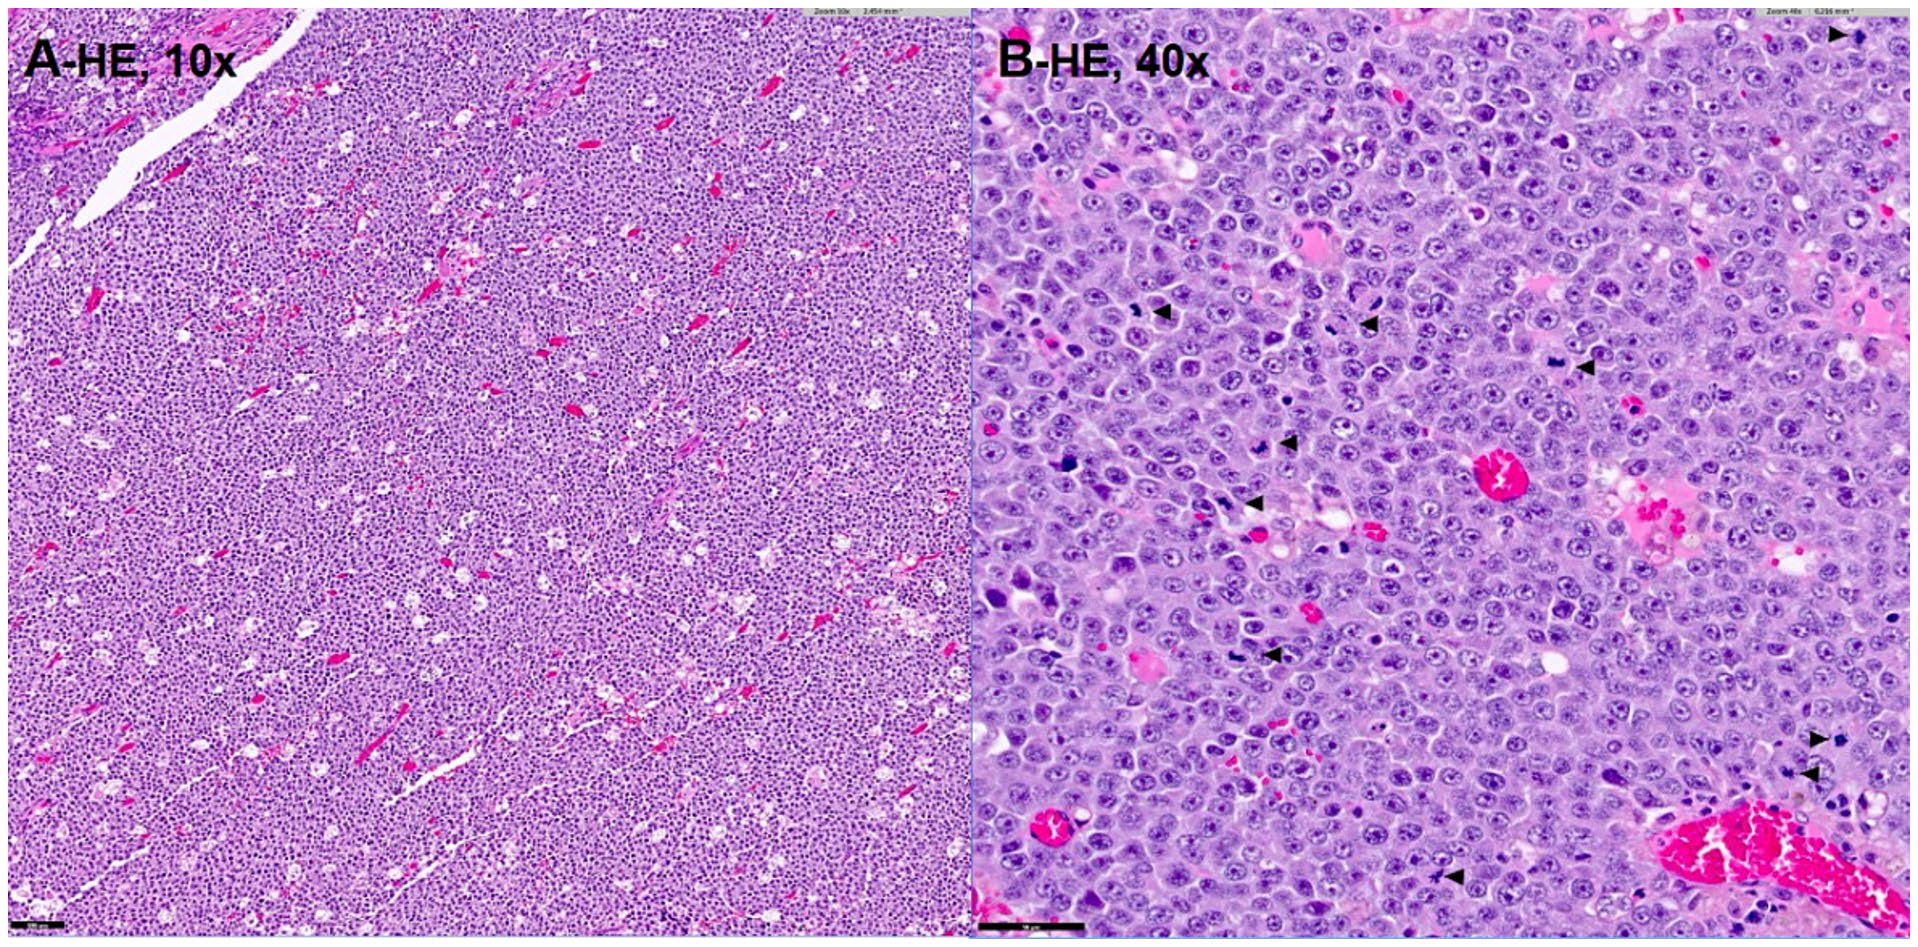

组织病理学检查显示一个细胞密集、未被包膜包裹的大单形圆形细胞肿瘤,具有显著的核异型性和高有丝分裂指数(下图)。肿瘤细胞呈片状和团块状排列,细胞边界清晰,少量嗜酸性细胞质,大圆形核,染色质细腻,核仁显著。观察到明显的细胞大小不一和核大小不一,核大小超过红细胞的两倍。这些特征与表现出侵袭性生物学行为的高级别淋巴瘤一致。肿块被完全切除,手术切缘较窄(<0.1毫米)。

↑ 组织病理学(AB)显示一个细胞密集、高级别的大细胞圆形细胞肿瘤,具有显著的核异型性和高有丝分裂指数(B;箭头)。

病理学检查显示,肿瘤细胞为单形性大圆形细胞,核异型性显著,有丝分裂指数高,初步与高分级淋巴瘤相似。然而,免疫组化结果排除了淋巴瘤和肾母细胞瘤的可能性,最终基于神经内分泌标志物的强阳性表达,确认为副神经节瘤。